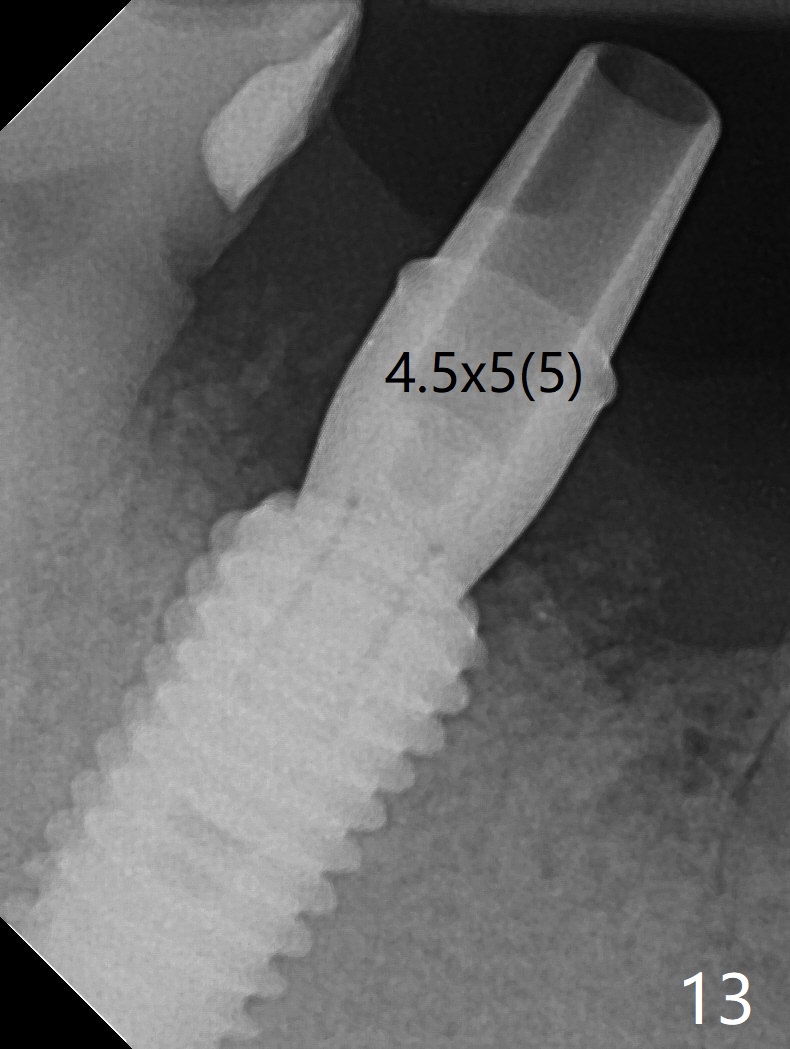

Although the tooth #30 has distobuccal root exposure (Fig.1 <), it is asymptomatic. In contrast the tooth #31 with the distoocclusal caries (*) is symptomatic. After use of 2 mm drill for 18 mm (lingual gingival margin), a calculated parallel pin is inserted (Fig.2 (D: 2 distal roots of the tooth #30)). It appears that a 11.5 mm long implant is appropriate for the site; a 5 mm cuff is expected. Following 4.8 mm drill, a 5.5x11.5 mm implant is placed initially (Fig.3) with an apical space (*) and clearance from the Inferior Alveolar Canal (red dashed line). The implant is placed deeper with placement of a 6.5x4(5) mm abutment and bone graft (*, Fig.4,5). After placement of collagen membrane over the graft, an immediate provisional is fabricated (Fig.6 P) with clearance from the opposing tooth (Fig.7 *). There is no bone loss 3.5 months postop (Fig.8). In fact the abutment has not been seated completely since its placement (Fig.4,5,8). The crown/abutment dislodges 3 years 3 months post cementation (Fig.9). The latter occurs for long incubation time because of opposing partial denture (Fig.10). After trimming proximal surfaces (Fig.11: arrowheads), the abutment remains incompletely seated (Fig.11) due to possible crestal bone interference (Fig.11 *). The smaller abutment by itself remains unseated (Fgi.12). One size small one is completely seated (Fig.13). Impression is taken. Two weeks later the abutment margin is supragingival. After screw torque at 20 Ncm, the crown is cemented with access hole. Excess cement is removed.